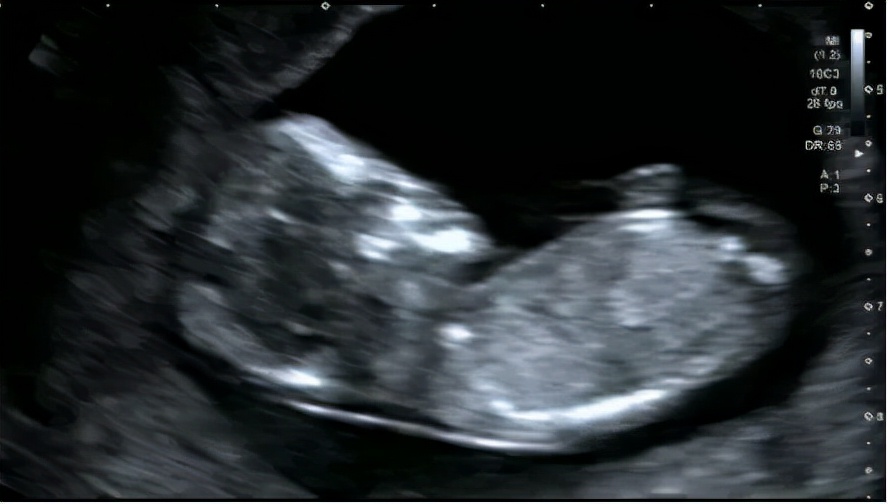

2月24日,今年28岁人工授精怀孕12周的小园妈妈来我院(广东省妇幼保健院、广东省儿童医院、广东省妇产医院)例行产检,孕11-13周产科彩色多普勒超声检查提示 胎儿发育异常:脑膜膨出 。在这一检查结果对于患有习惯性流产的小园妈妈犹如晴天霹雳。

产检发现宝宝 脑膜膨出